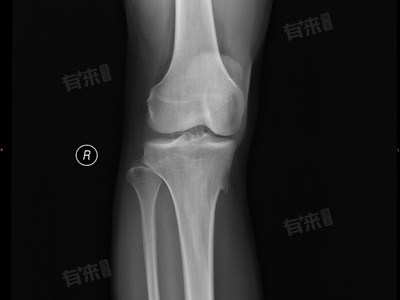

膝盖骨刺即膝关节骨刺,是一种常见的关节疾病,主要由于膝关节退行性变引起,治疗膝盖骨刺的方法多种多样,最佳治疗方案应根据患者的具体情况、骨刺的严重程度以及医生的建议来确定,常见的治疗方法有非手术治疗、手术治疗等。